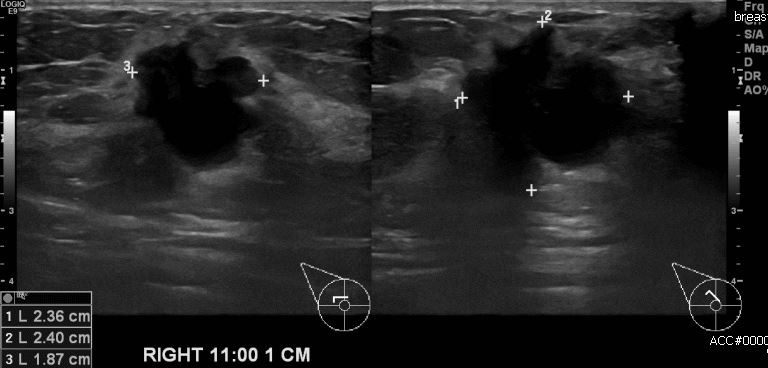

우측 유방에 멍울로 내원하신 30대 여성분으로 본원 초음파 시행 후 우측유방 11시

방향에서 1cm 떨어진 거리 의심스러운 멍울 조직검사 시행하여 우측 침윤성 유방암

진단 되었습니다.